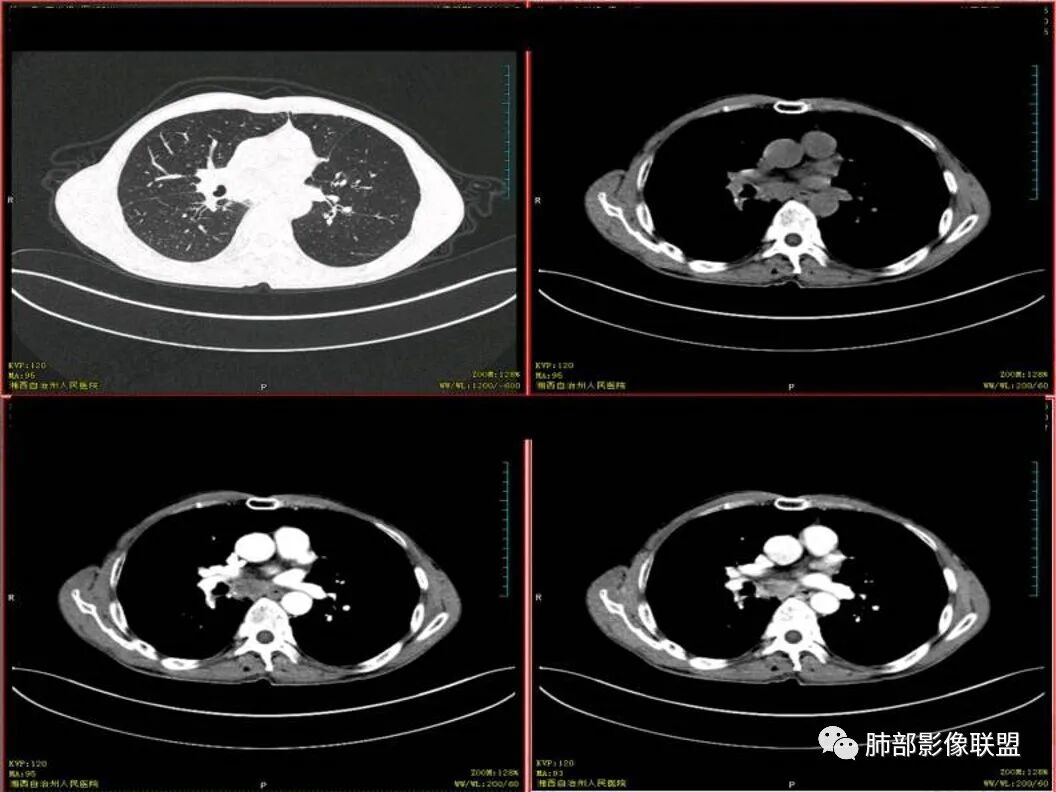

胸CT可见右肺下叶前基底段占位性病变,病灶周围可见周围不清毛玻璃影,病灶边缘可见分叶,呈膨胀性生长,纵隔窗可见病灶内呈偏心性坏死,增强扫描静脉期强于动脉期,纵隔隆突下淋巴结可见肿大坏死。

双上肺多发病灶,考虑结核(陈旧灶为主),右肺下叶前基底段占位,分叶、毛刺、胸膜牵拉,中央坏死,局部壁不光滑,前基底段支气管未见显示,不均匀强化,病灶远端阻塞性炎症,纵隔淋巴结肿大、融合。综合考虑恶性病变,鳞癌可能大。

临床 中年男性,咳嗽盗汗、老结核史,血沉高、t试验阳性,结核应该存在,cyf高4倍,价值怎么样待验证。影像 :两上肺实变加粗大索条灶,两肺野弥漫粟粒,考虑结核应该问题不大。重点分析右下病灶:隆突下淋巴结肿大,但伴钙化,有边缘强化?淋巴结融合又是恶性征像?右下肺病灶冠状位总体方正,横断位总体三角型,长毛刺、近端也有渗出、坏死彻底、空洞壁光滑锐利,似有边缘强化?看做薄壁空洞?以上符合炎性病灶。   支持恶性的征像 :冠状位的空洞似有壁结节,偏心坏死。   综合 ,右下肺鳞癌(偏心空洞+cfy)+两肺结核。

右下叶前基地段肿块,不规则边缘,周围树丫和长短毛刺,内部小空泡,强化后环形强化,纵膈淋巴结肿大,并有不规则环形强化和钙化,总体考虑感染性病变,结核病。

老年男性,既往有肺结核病史。影像双上肺病灶考虑陈旧性肺结核病灶,关键是右下肺团块影,从视频看,右下叶前段分支有堵塞,病灶局部膨隆,有分叶,周围有磨玻璃,但边界不大清楚,远端还有可以阻塞性炎征象,内部有偏远心端坏死,故考虑恶性可能性大。

结核和肺癌鉴别,因为淋巴结坏死疾病就这两种,坏死来看并不像小细胞肺癌。主病灶膨隆,增强后,壁厚薄不均,有壁结节感觉,首先是不能放弃的是肺癌这个诊断。具体哪一种还是主要看病理,建议支气管镜穿刺淋巴结的。

影像表现为 双肺上叶多发索条斑片影,可见支气管牵拉性扩张,考虑为陈旧肺结核纤维硬结灶。右肺下叶前基底段团块影膨隆生长,边界不清,呈分叶,毛刺,胸膜牵拉,支气管截断,中央区坏死明显,但未形成空洞,坏死区边缘光整,不均匀环形强化,隐约见壁结节。纵隔淋巴结肿大伴钙化,病灶远端见阻塞性炎症,结合CYFRA21-1偏高,应想到考虑恶性病变,鳞癌可能性大。